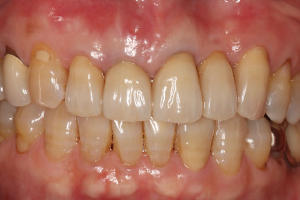

症例

オールセラミック(e-max)

治療前

治療後

治療前のレントゲン

治療後のレントゲン

歯肉退縮により、以前他院で製作されたセラミック冠の審美障害があります。また時々、根元が腫れていたとのこと。前歯4本すべて根管治療を行い、ファイバーコアを入れてからオールセラミック(e-max)で修復しました。術後のレントゲンでは根尖性歯周炎が改善しています。

5ヵ月・20回

¥600,000